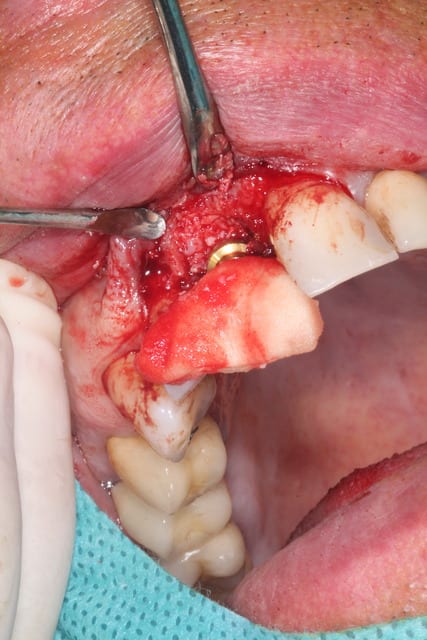

J'attendais d'avoir terminé le cas pour vous le présenter.

Il s'agit d'une EIIMCI avec comblement du gap.

J'ai utilisé un pilier plein que je n'ai pas déposé depuis la chirurgie.

Aurait-on obtenu le même résultat avec un pilier transvissé?